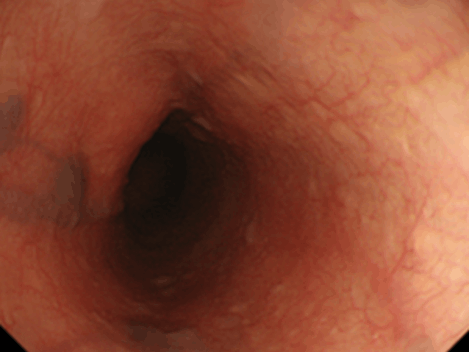

投薬治療でわずかな縦走溝・軽度白斑の状態に改善。消化管からの血液は粘膜で吸収された栄養素を多く含んでいるため、そのほとんどは門脈を介して肝臓へといたります。そして肝臓は、これを代謝して体に必要な形に変えたり、有害な成分を無毒化したり、栄養を蓄えたりするという役割を担っています。